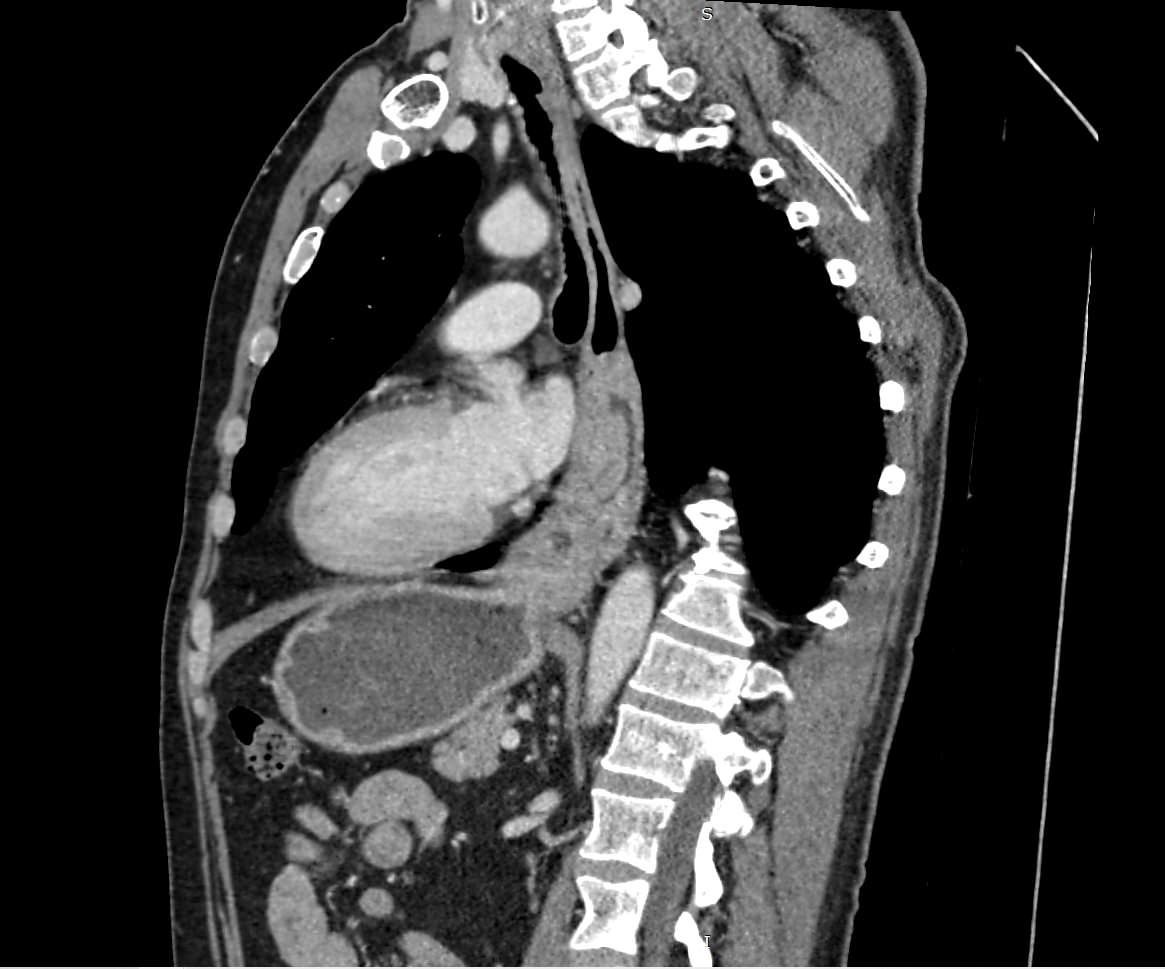

Компьютерная томография является высокоинформативным методом лучевой диагностики, который применяется для выявления заболеваний пищевода, используется при планировании оперативного лечения и для оценки успешности проведенной операции на пищеводе.

Данное исследование также позволяет оценить состояние соседних органов и тканей, включая легкие и регионарные лимфоузлы, что бывает важно для установления степени распространенности патологического процесса.

В нашей клинике исследование выполняется на новейшем 128-срезовом мультиспиральном компьютерном томографе экспертного уровня TOSHIBA AQUILION CXL. Аппарат послойно сканирует анатомическую область пищевода, выполняя срезы с минимальной толщиной от 0,5 мм, затем преобразует полученные данные в трехмерные изображения исследуемой зоны.

Томограф оснащен высокочувствительными детекторами, которые выполняют до 128 срезов анатомической области за секунды, обеспечивая превосходный уровень детализации изображений и высокое качество обследования. Кроме того увеличенное количество срезов сокращает время обследования и позволяет максимально снизить лучевую нагрузку на пациента.